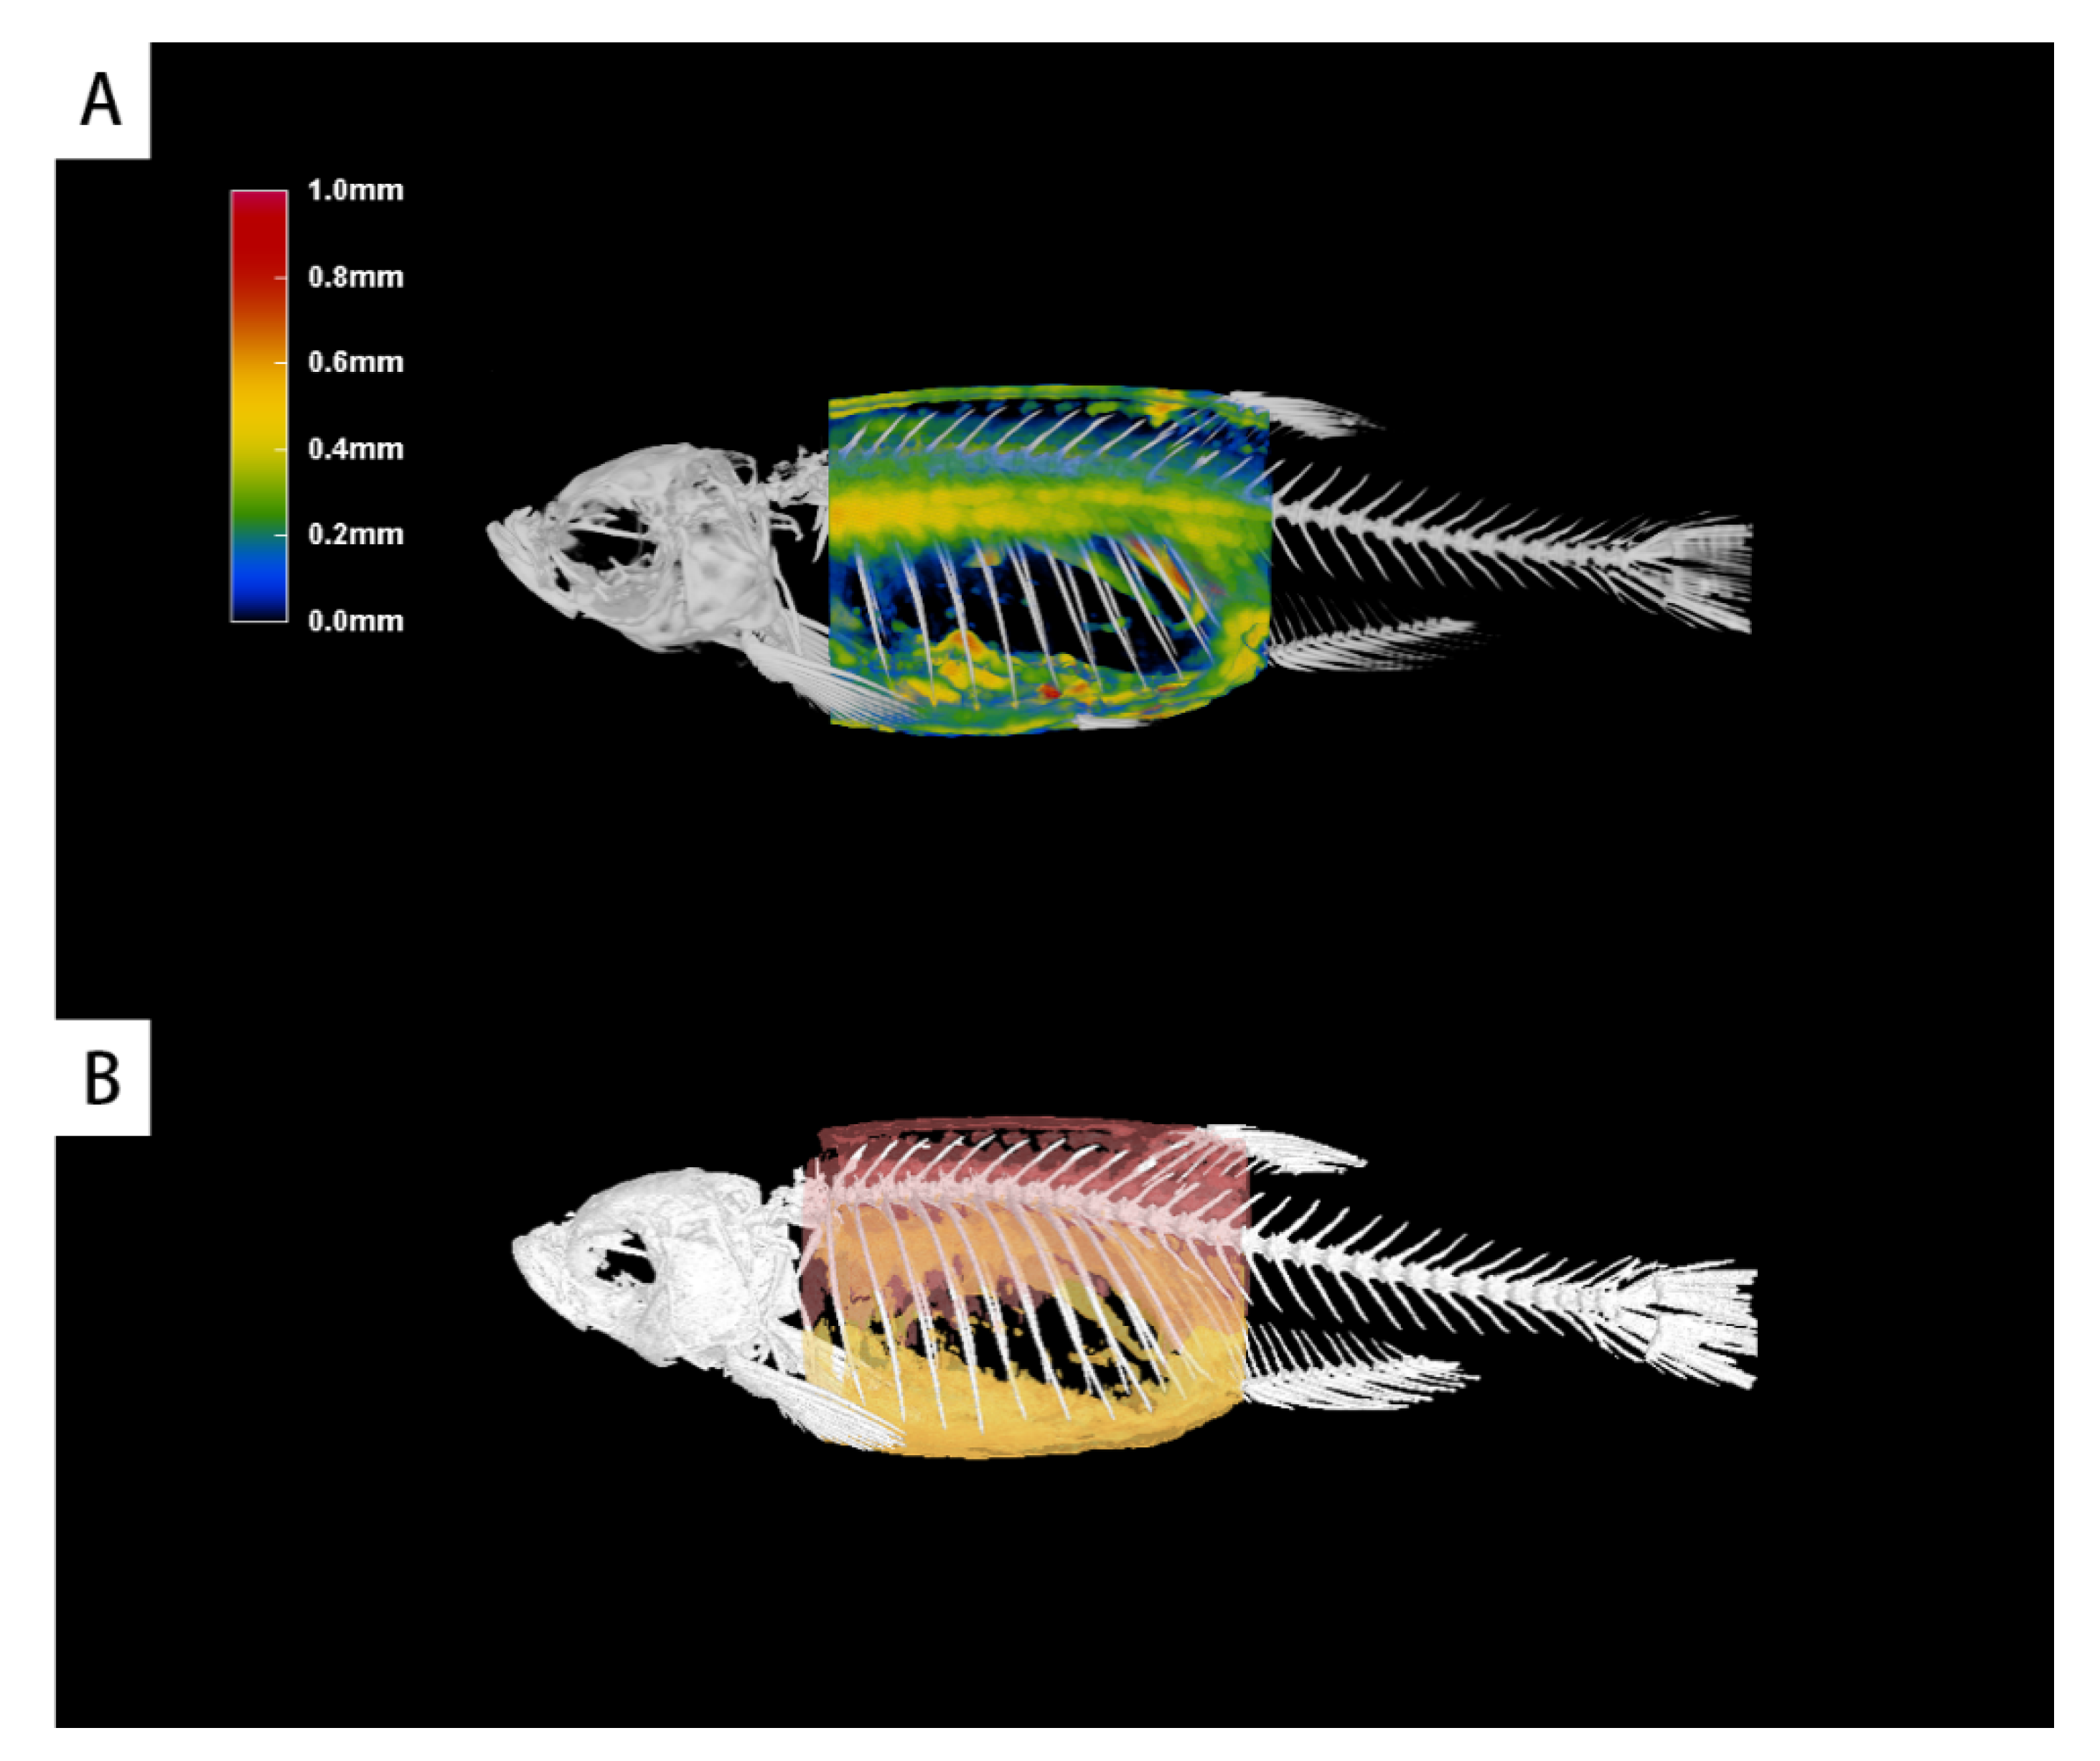

3.5. 3D Graphical Rendering

3.3. Scanning the Standard Plane of Trunk Adipose Tissue

3.4. Quantitative Calculation of Trunk Adipose Tissue